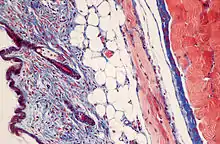

Masson's trichrome stain

Masson's trichrome is a three-colour staining protocol used in histology. The recipes evolved from Claude L. Pierre Masson's (1880–1959) original formulation have different specific applications, but all are suited for distinguishing cells from surrounding connective tissue.

Most recipes produce red keratin and muscle fibers, blue or green collagen and bone, light red or pink cytoplasm, and dark brown to black cell nuclei.